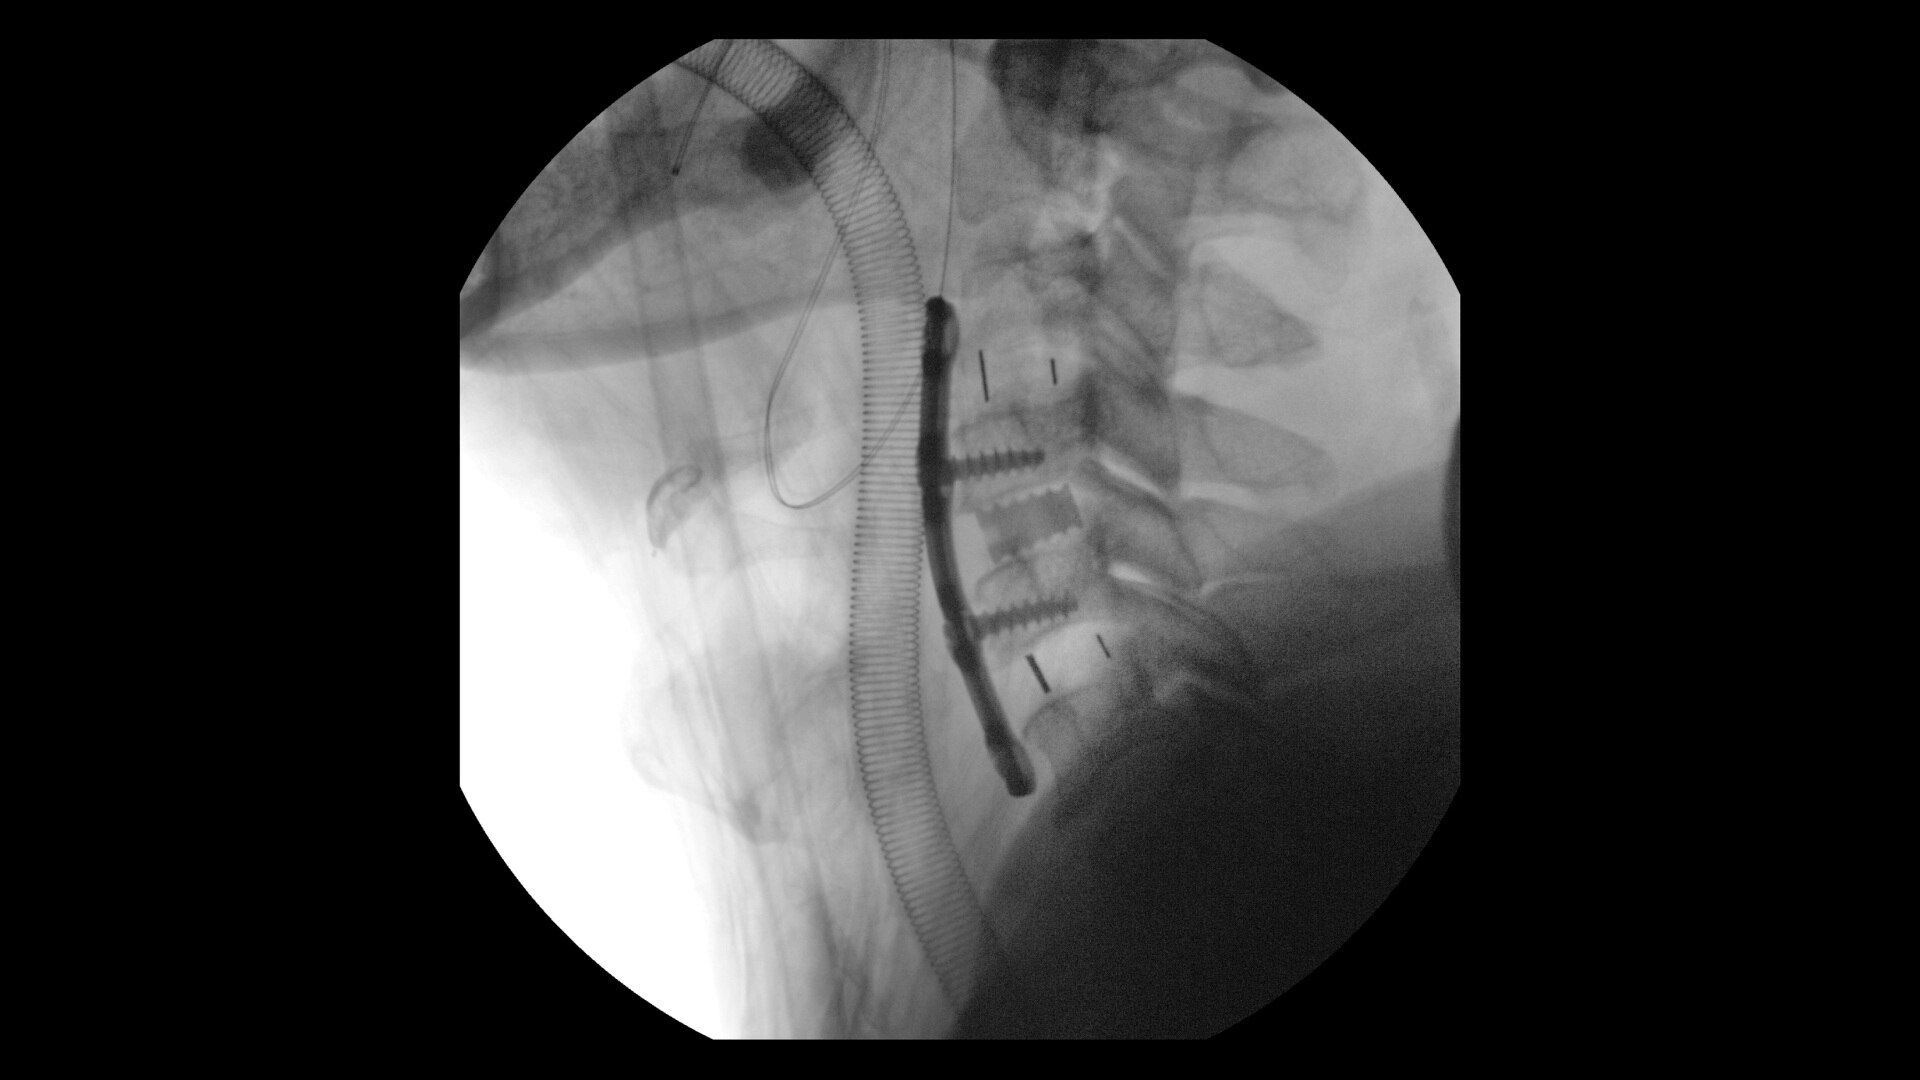

Avec cette nouvelle application d’imagerie des surfaces de l’os cortical, basée sur l’application radiale Zero TE (ZTE), réalisez tous vos examens d’imagerie osseuse et ajoutez une valeur clinique considérable à vos examens orthopédiques.

Disponible pour toutes les anatomies sans rayonnement ionisant, oZTEo capture la morphologie osseuse, les calcifications, l’ossification et les fractures, complète les examens IRM conventionnels des tissus mous avec un alignement parfait et fournit une imagerie isotrope 3D à l’aide d’une acquisition radiale ZTE, avec une insensibilité au mouvement inhérente. À utiliser avec Volume Illumination pour un rendu 3D réaliste.

Lorsque oZTEo est inclus dans un examen IRM, les images de l’os cortical sont parfaitement alignées avec la série des tissus mous, ce qui en fait une solution d’imagerie tout-en-un pour la plupart des examens musculosquelettiques de routine.